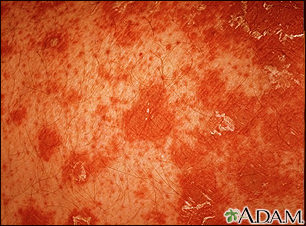

Primer plano de la pitiriasis rubra pilaris

La pitiriasis rubra pilaris es una condición cutánea poco común caracterizada por parches color salmón con escamas (queratodermia palmoplantar). Un signo característico de esta condición es el taponamiento con queratina de los folículos pilosos. Típicamente el folículo aparece rodeado de una coloración rojo-naranja.